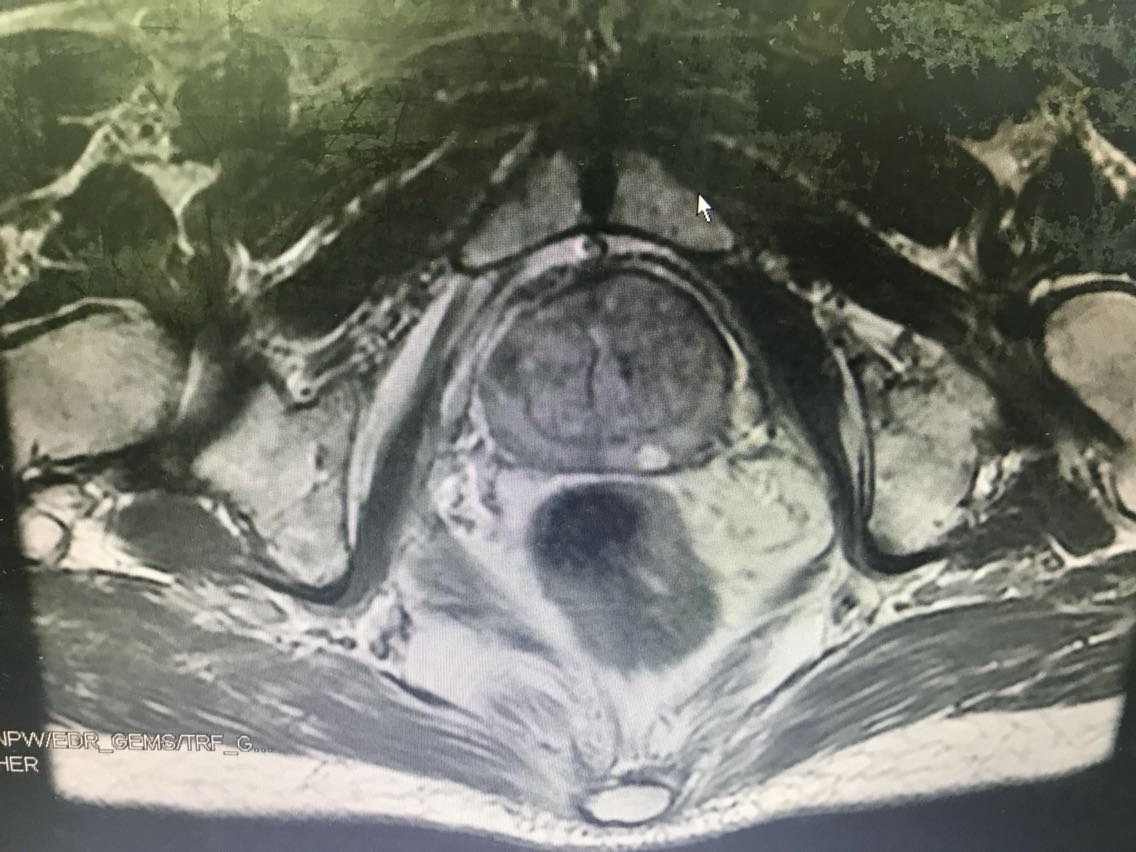

患者男性,77岁。 主诉:血尿7+月 现病史:入院前7+月,患者出现血尿,于外院体检查示PSA升高(10.62),服药血尿控制(具体药物不详),无尿频、尿急、下腹疼痛等不适,为求进一步诊治于我院门诊就诊,查前列腺MRI:前列腺尖部右侧中央带结节及9-10点结节,多系前列腺癌。门诊行前列腺穿刺活检示:编号1、2、3、4、5、6查见前列腺腺癌,Gleason评分4+3=7分。门诊以“前列腺癌”收入我科。患病来精神、睡眠、食欲可,大小便无异常,体重无明显变化。 既往史无特殊。

查体:腹部平软,无压痛及反跳痛,双肾及输尿管走行区无压痛,肾区无叩痛。直肠指检:前列腺Ⅱ°大,双侧质硬,右侧叶扪及约1cm硬结。 辅助检查: 前列腺MRI(2018-6-14,本院):前列腺尖部右侧中央带结节及9-10点结节,多系前列腺癌,累及右侧外周带 前列腺穿刺活检示(2018-6-28,本院):编号1、2、3、4、5、6查见前列腺腺癌,Gleason评分4+3=7分。